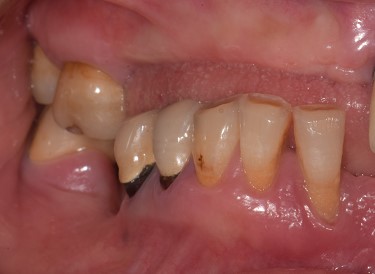

Una paziente di 65 anni si presentava presso la nostra clinica con ampie aree edentule (1° e 3° quadrante), un ponte con mobilità nel 2° quadrante e denti inferiori con scarso supporto parodontale ad eccezione del dente 46 (Fig. 1 a,b,c,d). Dopo un'accurata anamnesi ed esame della CBCT (CS9600®, Carestream Dental, Atlanta, USA) (Fig. 1d), si optava per estrarre le radici e i denti con una prognosi sfavorevole, lasciando 4 molari che credevamo potessero essere conservati (denti 16,17, 26 e 47) al fine di mantenere la dimensione verticale di occlusione (DVO) originale. Si progettava il posizionamento di 12 impianti: 6 impianti nella mascella e 6 nell'arcata inferiore.

Situazione pre operatoria 2

Fig. 1(b)

Situazione pre operatoria 3

Fig. 1(c)

Situazione pre operatoria 4

Fig. 1(d) Situazione pre-operatoria.